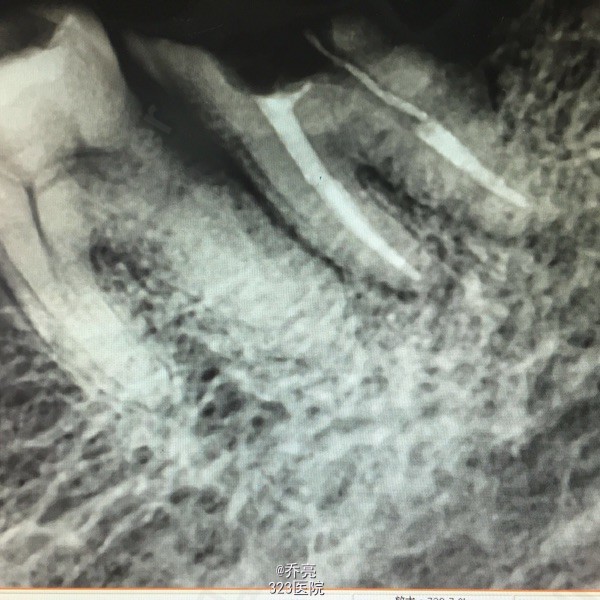

左下7金属牙冠松动,不密合,去除后牙体缺损,面积较大,探(+)冷(+)松动1度,叩(+-) 右上1松动2度 x线示:左下7缺损及髓,根尖无明显异常 右上1根尖阴影

诊断:左下7慢性牙髓炎 右上1牙槽骨吸收 建议:左下7RCT+桩+冠 右上1抜除后修复 处理:左下7清理根管,双氧水冲洗,干燥置木溜油棉,ZOE暂封 右上1局麻下拔除,牙槽窝搔刮,恢复牙槽窝,咬干棉球止血